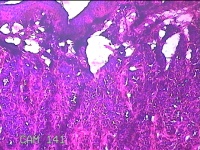

右侧头皮结节

性别

男

年龄

28岁

临床诊断

皮肤良性肿瘤

一般病史

发现右侧头皮结节3个月余,无明显疼痛及不适。

标本名称

大体所见

灰白暗红色组织1.5x1.2x0.8cm一块,表面带梭形皮肤1.5x1cm,皮下见结节1.5x1x0.3cm一个,结节表面有少许毛发,切开结节呈实性,切面灰白粉红色,质软。